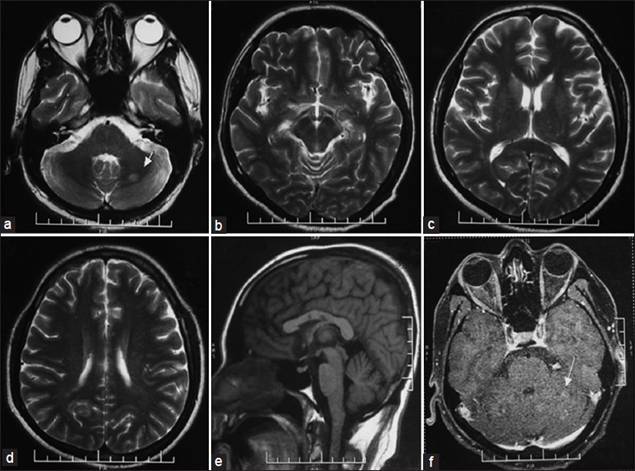

Về mặt chẩn đoán, chụp cộng hưởng từ (MRI_Magnetic resonance imaging) trên một bệnh nhân mắc bệnh Agiostrongyliasis thường có biểu hiện hình ảnh tăng nhiều nốt nhỏ trong nhu mô não và tăng tuyến tính trong phần vùng màng mềm bao bọc quanh não và tủy sống. Độ phân giải hoàn toàn của các hình ảnh MRI bất thường xảy ra điển hình sau 4 - 8 tuần. Hình ảnh đa nốt cũng được phát hiện trên phim chụp MRI của nhu mô phổi, điều này có thể phản ánh có sự hiện diện giun trong các cơ quan phủ tạng.

H5